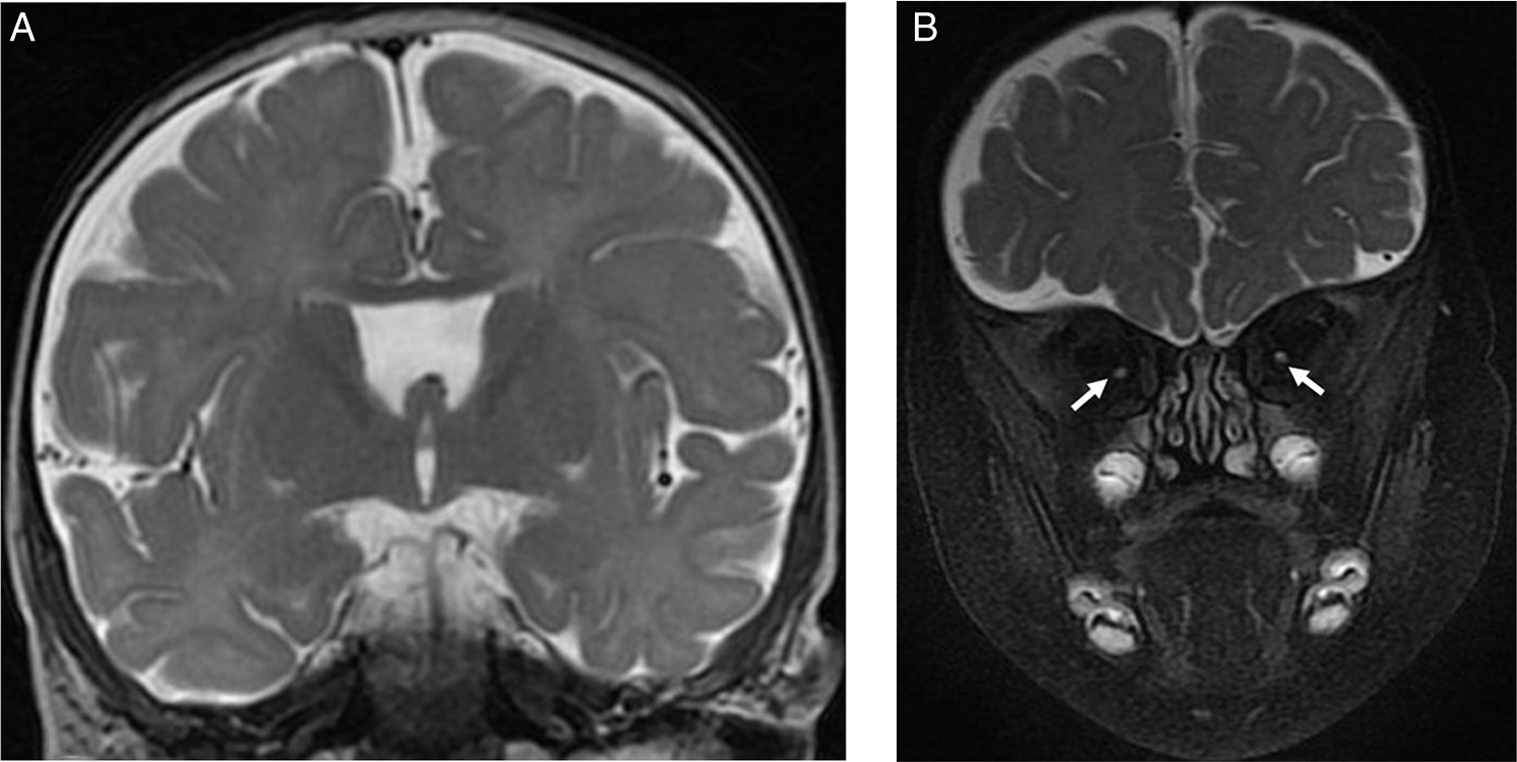

Septo-optic-pituitary dysplasia (SOD) is a neurodevelopmental abnormality that consists of optic nerve(s) hypoplasia (ONH) in association with hypopituitarism and/or midline brain abnormalities (absent septum pellucidum and/or abnormal corpus callosum) (Figures 1 and 2). In addition, neuronal migration disorders (NMD) (Figure 3) have been reported in some patients with SOD. ONH may also occur in isolation. Reference Garcia-Filion and Borchert1,Reference Webb and Dattani2

Figure 1: Brain MRI images of a 7-month-old male with severe bilateral visual impairment. (A) Coronal T2-weighted image showing absent septum pellucidum. (B) Coronal fat saturated T2-weighted image of the orbits showing small intraorbital optic nerves bilaterally (arrows).

There were 128 patients (M = 70) with ONH/SOD who had neuroimaging studies. Their median age (interquartile range) at study end was 12.2 (7.4–17.6) years. Their neuroimaging characteristics and findings are displayed in Table 1. Figures 1 –3 show some of the abnormal neuroimaging features.